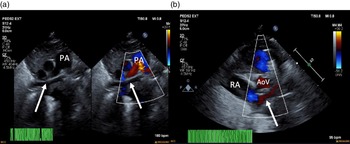

On arrival, the patient remained on an alprostadil infusion at 0.1 mcg/kg/minute, with oxygen saturations persistently in the 50’s despite ongoing respiratory support with nasal continuous positive airway pressure with FiO2 100%. The patient was immediately intubated but remained significantly desaturated. Repeat echocardiogram was obtained (Fig 1), which revealed the absence of pulmonary veins entering the atrium and absence of dilated pulmonary veins or large vertical vein. There was all right to left shunting across an unrestrictive atrial communication, and there was a large patent ductus arteriosus with predominantly right to left flow. A trivial pulmonary vein confluence was seen posterior to the left atrium. The right ventricle was dilated and the left ventricle was apex forming but appeared underfilled. Given that discrete pulmonary veins or venous drainage could not be delineated by echocardiography, cardiac CT scan was emergently obtained. Cardiac CT revealed a trivial pulmonary venous confluence with small left and right veins posterior to the left atrium; however, no discrete connection to the heart was identified (Fig 2). Due to the near atretic nature of this patient’s pulmonary veins and common pulmonary vein and lack of identified collaterals, extensive multidisciplinary discussions were held between Cardiology, Cardiac Intensive Care, Radiology, and Cardiothoracic Surgery teams. Ultimately, it was determined that there was no viable operative repair, and the decision was made between the family and the medical team to proceed with withdrawal of care. The patient was transferred back to the cardiothoracic ICU, compassionately extubated, and died shortly thereafter. An autopsy was performed which confirmed the absence of any pulmonary venous connection to the left atrium. There was a trivial pulmonary venous confluence superior to the left atrium as noted on the echocardiogram and CT, with a trivial vein that appeared to drain from the confluence to the innominate vein. No dilated pulmonary veins were demonstrated by autopsy. On gross examination, the lungs had a diffusely nodular appearance and histological examination revealed findings consistent with cystic lymphangiectasia.

Figure 1. ( a ) 2D echocardiogram and colour echocardiography. Seen (arrows) is a trivial pulmonary venous confluence coursing superior to the left atrium (not seen). ( b ) Colour echocardiography. Underfilled left atrium (arrow) seen demonstrating the absence of pulmonary venous return to the left atrium; notably the right atrium is dilated. AoV = aortic valve; PA = pulmonary artery; RA = right atrium.